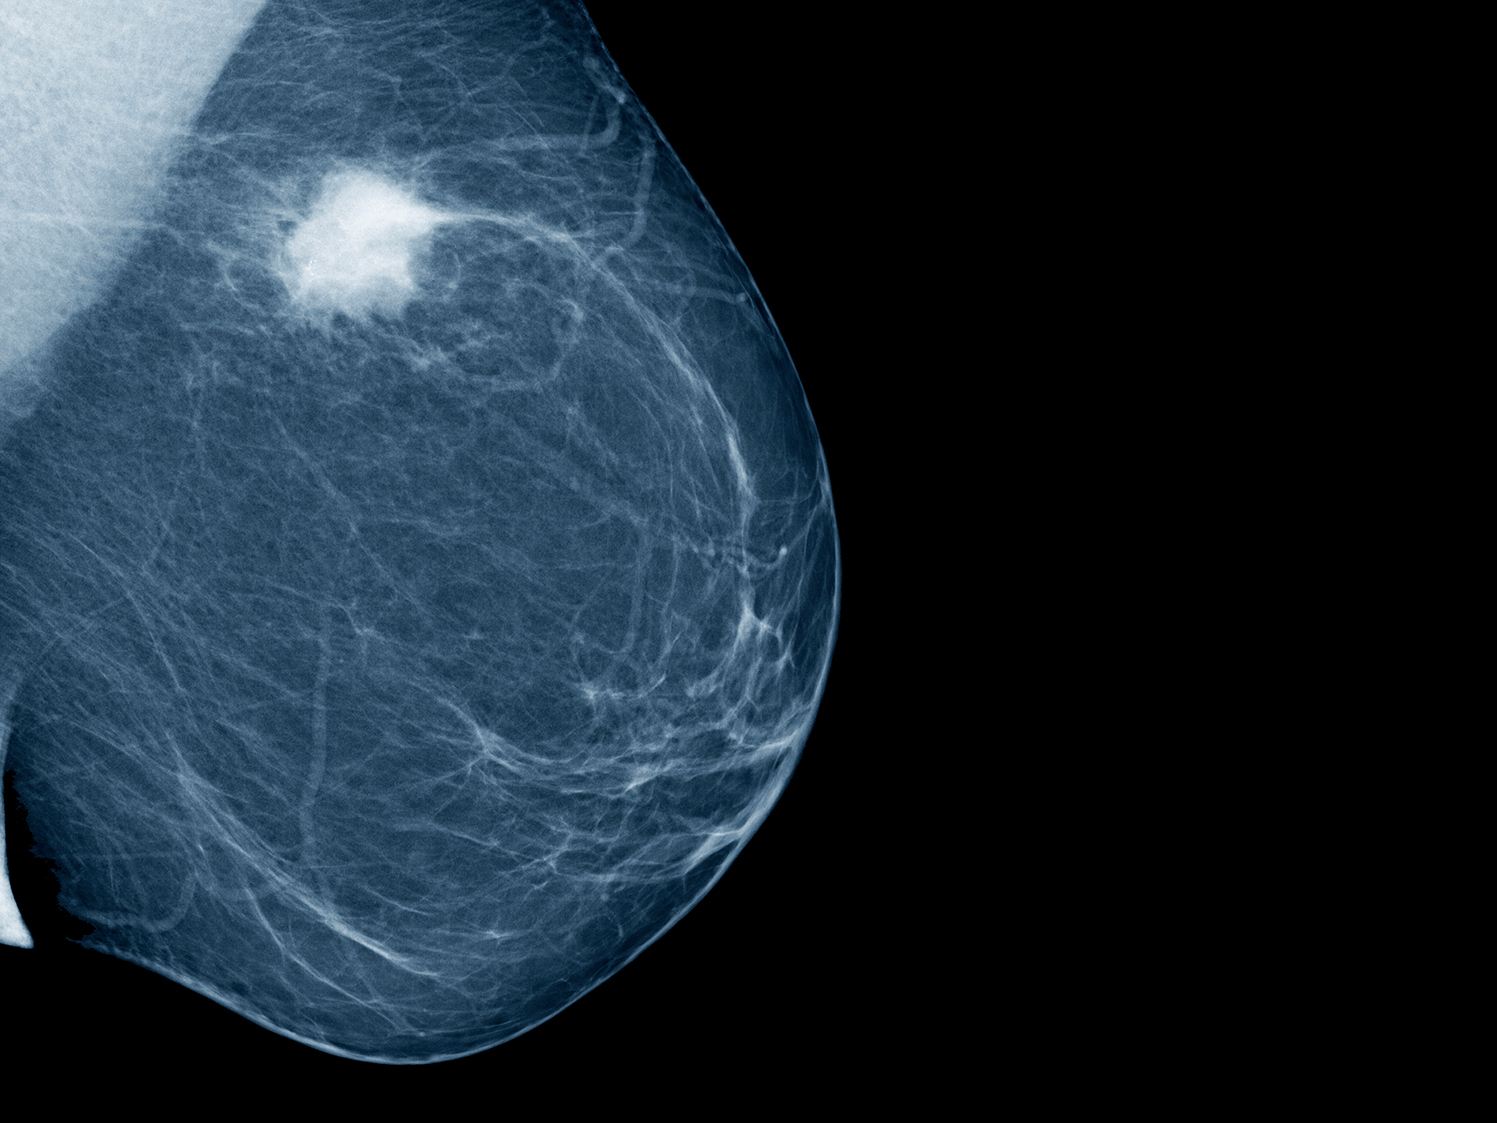

УЗИ молочных желез — информативный и безопасный метод диагностики, с помощью которого можно точно оценить состояние желез, обнаружить доброкачественные и злокачественные образования, уточнить диагноз. Это доступное по цене исследование безвредно и не несет лучевой нагрузки. Оно имеет большое значение в ранней диагностике заболеваний и нередко применяется в профилактических целях. На УЗИ может направить маммолог, онколог, эндокринолог, гинеколог.

Сделать УЗИ молочных желез можно в качестве первичной диагностики и для уточнения уже предполагаемого диагноза. Метод основывается на способности высокочастотных ультразвуковых волн с различной скоростью отражаться от тканей с разной плотностью.

С помощью ультразвуковой диагностики можно обнаружить следующие заболевания:

- рак;

Для оценки кровотока в тканях молочных желез используется доплерография. Данные, полученные в результате биопсии под контролем УЗ-аппарата, могут сказать о природе и характере образований в молочных железах.

Диагностировать липому может врач хирург после визуального осмотра и пальпации места новообразования. По рекомендации врача может потребоваться УЗИ мягких тканей, маммография или биопсия с цитологическим или гистологическим исследованием.

По рекомендации врача может потребоваться УЗИ мягких тканей, маммография или биопсия с цитологическим или гистологическим исследованием.